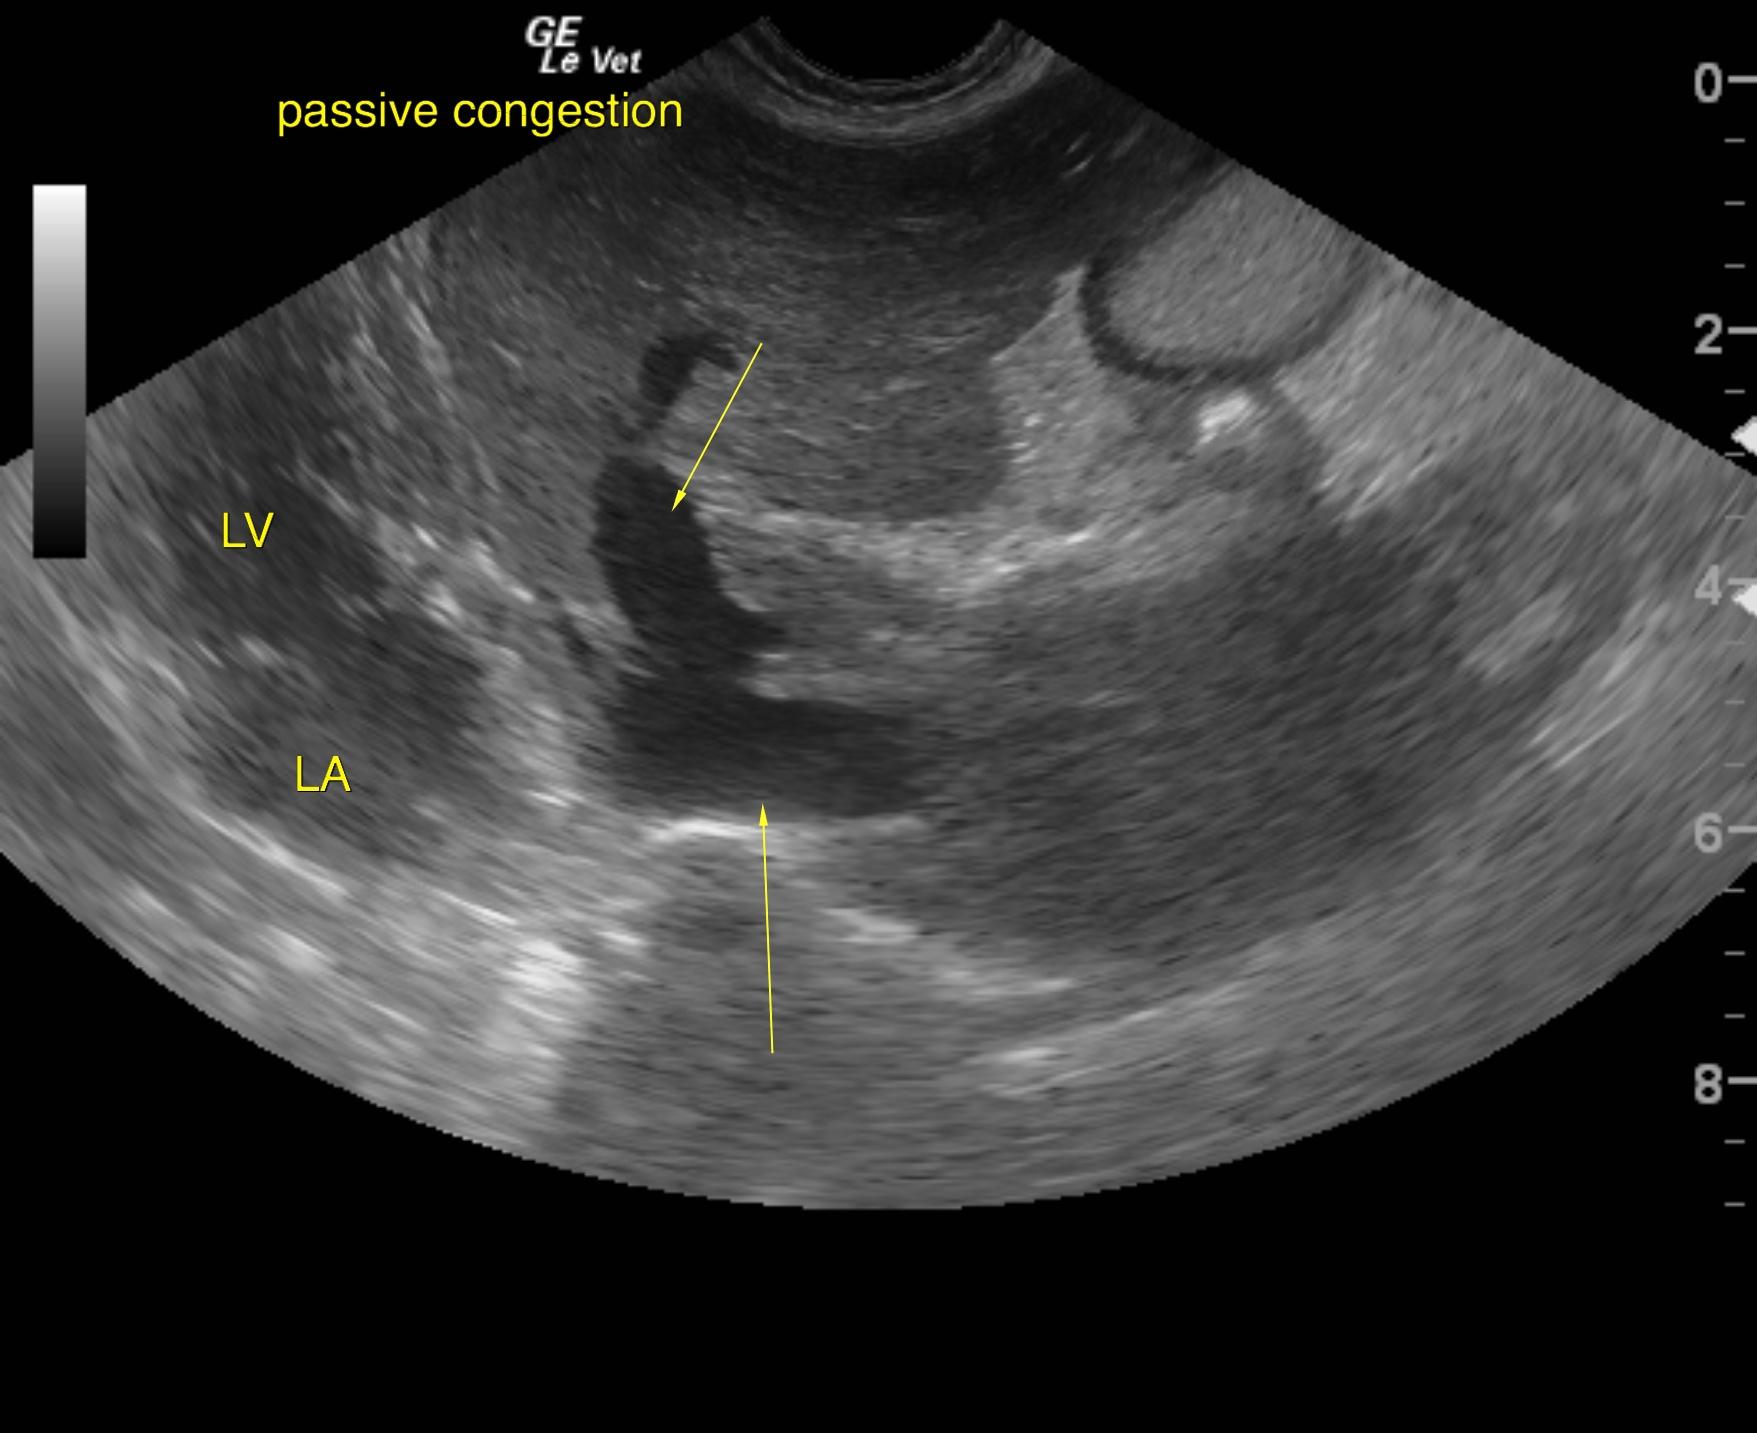

A 10-year-old NM Pomeranian was presented for evaluation of decreased appetite, increased respiratory rate and effort, abdominal distention, and syncopal episodes for the past two weeks. Abnormalities on physical examination were Grade V/VI heart murmur, clear lungs with increased respiratory rate and effort, a palpable fluid wave. Urinalysis showed 3+ proteinuria. Abnormalities on CBC and serum biochemistry were leukocytosis and hypoproteinemia. Survey radiographs showed mild pleural effusion, severe cardiomegaly, and decreased serosal detail within the abdomen.